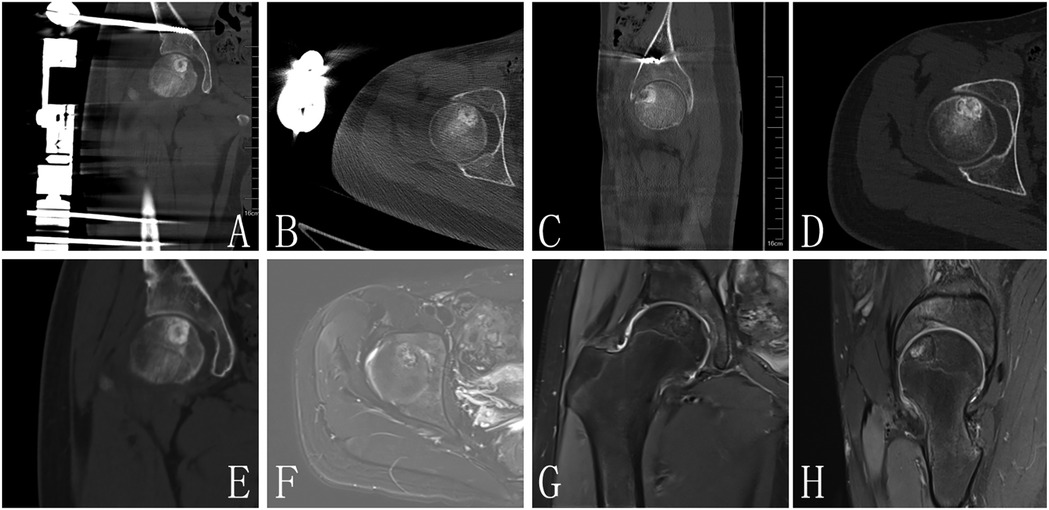

Figure 2

Eight medical images labeled A to H show various angles and cross-sections of a hip joint, highlighting the bone structure and surrounding tissues. Each image focuses on different aspects and orientations, capturing a circular or oval feature within the joint area.

Figure 2. (A–C) Are postoperative images, CT (D,E) and MRI (F–H) of 1 year FU demonstrated no evidence of lesion recurrence in the femoral head, with radiological signs indicating complete resolution of the previous lesion.

At the one-year follow-up, CT and MRI evaluations demonstrated no evidence of lesion recurrence in the femoral head, with radiological signs indicating complete resolution of the previous lesion (Figure 4). The bone density in the formerly affected area had normalized, confirming satisfactory osteogenesis.